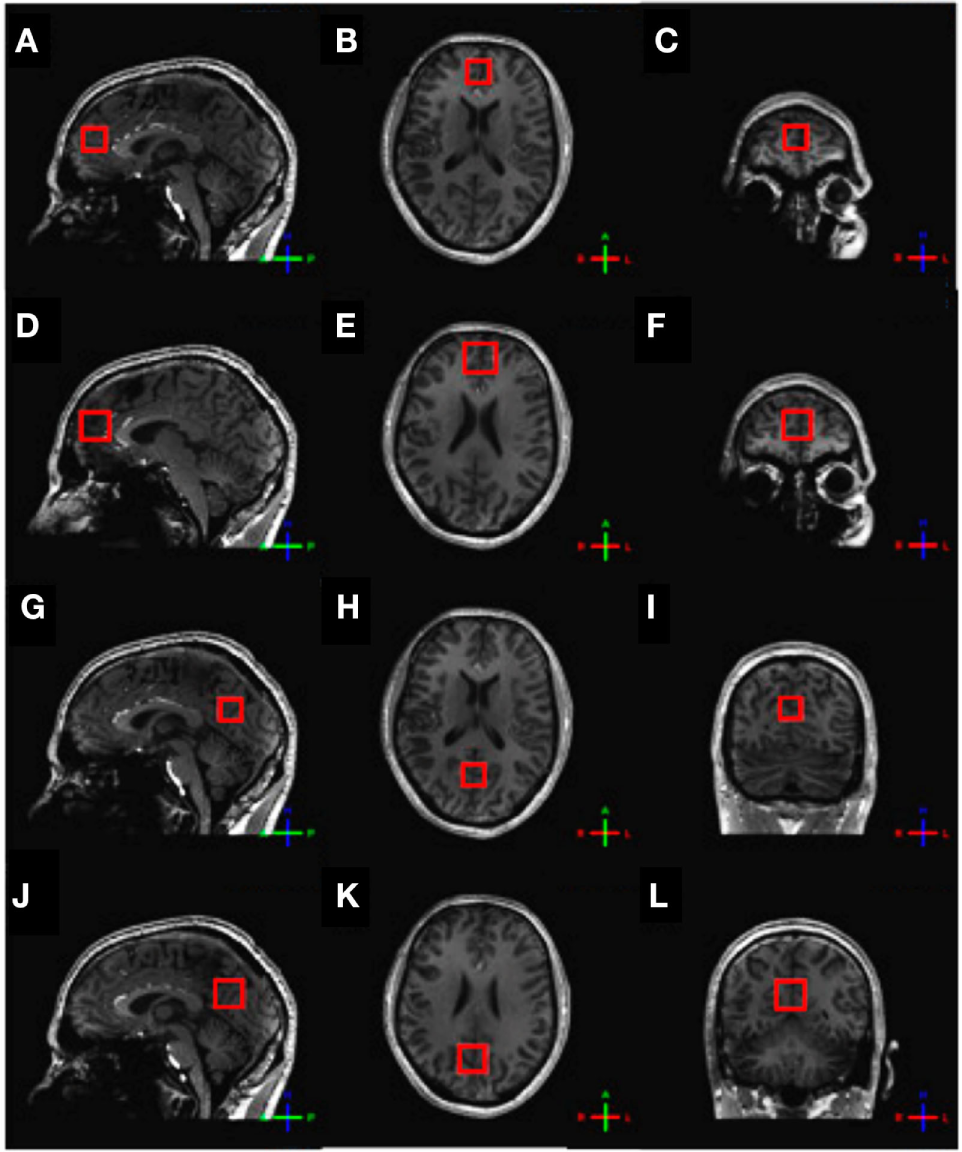

For the assessment of glutamate, 1H-MRS experiments were conducted using a sLASER sequence (semi-localized by adiabatic selective refocusing; TE = 28 ms, 32 averages, TR = 5 s) (Figure 1A). Voxels (2 cm × 2 cm × 2 cm) were located in the medial prefrontal and medial occipital lobe (Figure 2). Non-water-suppressed spectra were obtained for quantification (carrier frequency was set to the chemical shift of H2O, acquisition time = 10 s).

Figure 2

Voxel placement. (A) Frontal sLASER voxel, sagittal view; (B) frontal sLASER voxel, axial view; (C) frontal sLASER voxel, coronal view; (D) frontal MEGA-sLASER voxel, sagittal view; (E) frontal MEGA-sLASER voxel, axial view; (F) frontal MEGA-sLASER voxel, coronal view; (G) occipital sLASER voxel, sagittal view; (H) occipital sLASER voxel, axial view; (I) occipital sLASER voxel, coronal view; (J) occipital MEGA-sLASER voxel, sagittal view; (K) occipital MEGA-sLASER voxel, axial view; (L) occipital MEGA-sLASER voxel, coronal view [from Ref. (22)].

GABA-edited 1H-MRS experiments were conducted using a MEGA-sLASER sequence (TE = 74 ms, 64 averages, TR = 4 s) (Figure 1B) (31). Voxels (2.5 cm × 2.5 cm × 2.5 cm) were located in the medial frontal and medial occipital region (Figure 2). Prior to the MRS exams, second order B0 shimming was applied using the FASTERMAP algorithm at the voxel of interest (30, 32). Second, at this location, a high B1 field was generated to minimize chemical shift displacement artifacts (33). The highest possible B1 field was generated by optimizing the phase of both transmit channels to locally assure constructive B1 interferences (34).